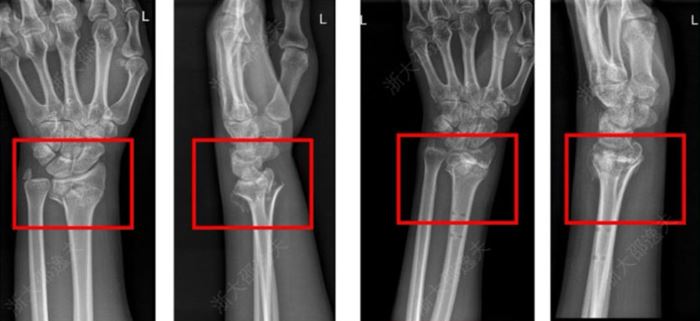

En la conferencia de prensa, el equipo destacó el caso de un joven trabajador con una fractura conminuta de muñeca.

El tratamiento estándar habría requerido una gran incisión para implantar placas y tornillos metálicos, con riesgos de daño nervioso, adhesión de tejidos y una segunda cirugía un año después para retirar el material.

Con “Bone 02”, los cirujanos pudieron unir los fragmentos óseos en solo tres minutos, utilizando una incisión de 2-3 centímetros para inyectar el pegamento. Un seguimiento de tres meses mostró la recuperación total de la función de la muñeca, sin complicaciones.

Utilizando “Bone 02” en una persona que sufrió una fractura en la muñeca, los cirujanos pudieron unir los fragmentos óseos en solo tres minutos, utilizando una incisión de 2-3 centímetros para inyectar el pegamento. Un seguimiento de tres meses mostró la recuperación total de la función de la muñeca, sin complicaciones. Crédito de imagen: Dr. Lin Xianfeng